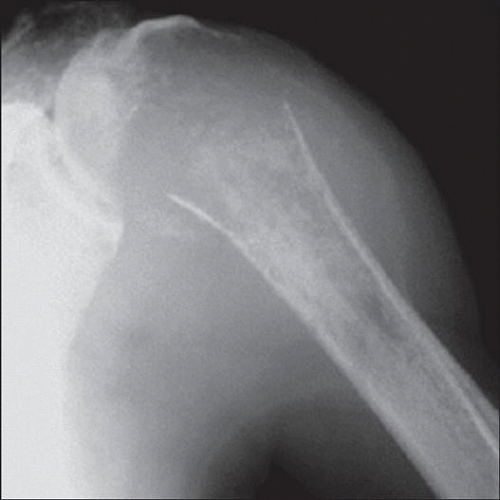

Рентгеновские снимки саркомы плечевого сустава